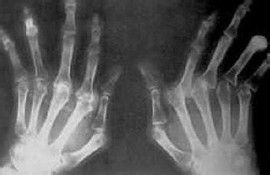

急性痛风三大明显症状——关节呈现出的病态反应

急性痛风病的发作是一次比一次严重的,甚至有剧痛的现象出现,患病的关节部位出现肿胀,局部发热,明显的皮肤暗红,有光泽现象,急性痛风病发的部位主要出现在患者的足弓,膝关节,脚趾手指,腕关节,手腕以及踝关节等地。